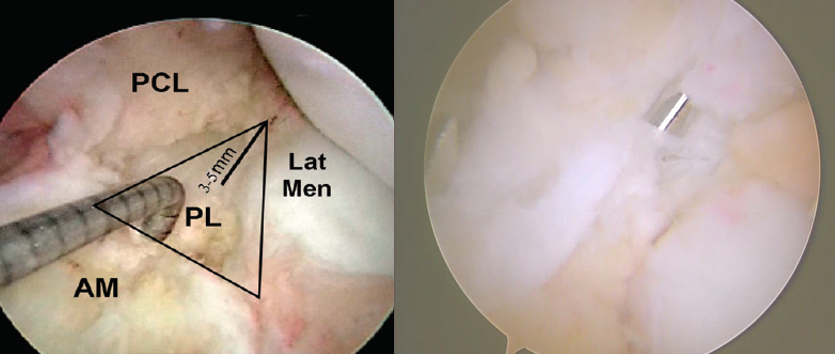

胎儿膝关节显示:两个功能束(AM,PL)

LFC为股骨外髁

关节镜显示AM,PL

尸体标本显示AM,PL

伸直时AM,PL的股骨点垂直排列,两束平行。

屈曲90°时,AM,PL的股骨点平行,两束交叉

膝关节屈曲90 °时PL松弛,而伸直时PL紧张状态

辅助内侧入路钻PL股骨隧道

屈曲90 °,导针在前侧关节软骨边缘后方5-7MM,上方3MM进入,屈曲110 °钻隧道。用直径6或7MM的钻头。

胫骨隧道:PL在55 ° AM在45 °在胫骨皮质上,PL入点位于AM入点的远端后内侧。PCL,外侧半月板根部和AM的止点构成三角,PL位于距其后角大约3-5MM,探针是单束重建的位置。

AM股骨隧道:在PL后侧边缘后方大约2MM,可以由胫骨隧道建立,直径一般7-8MM。